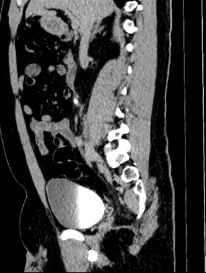

Chẩn đoán hình ảnh mô mềm tiên tiến cho vùng bụng.

Tăng cường độ tương phản I-ốt.

Hỗ trợ đánh giá an toàn cho bệnh nhân.

Đảm bảo hình ảnh chất lượng cao.